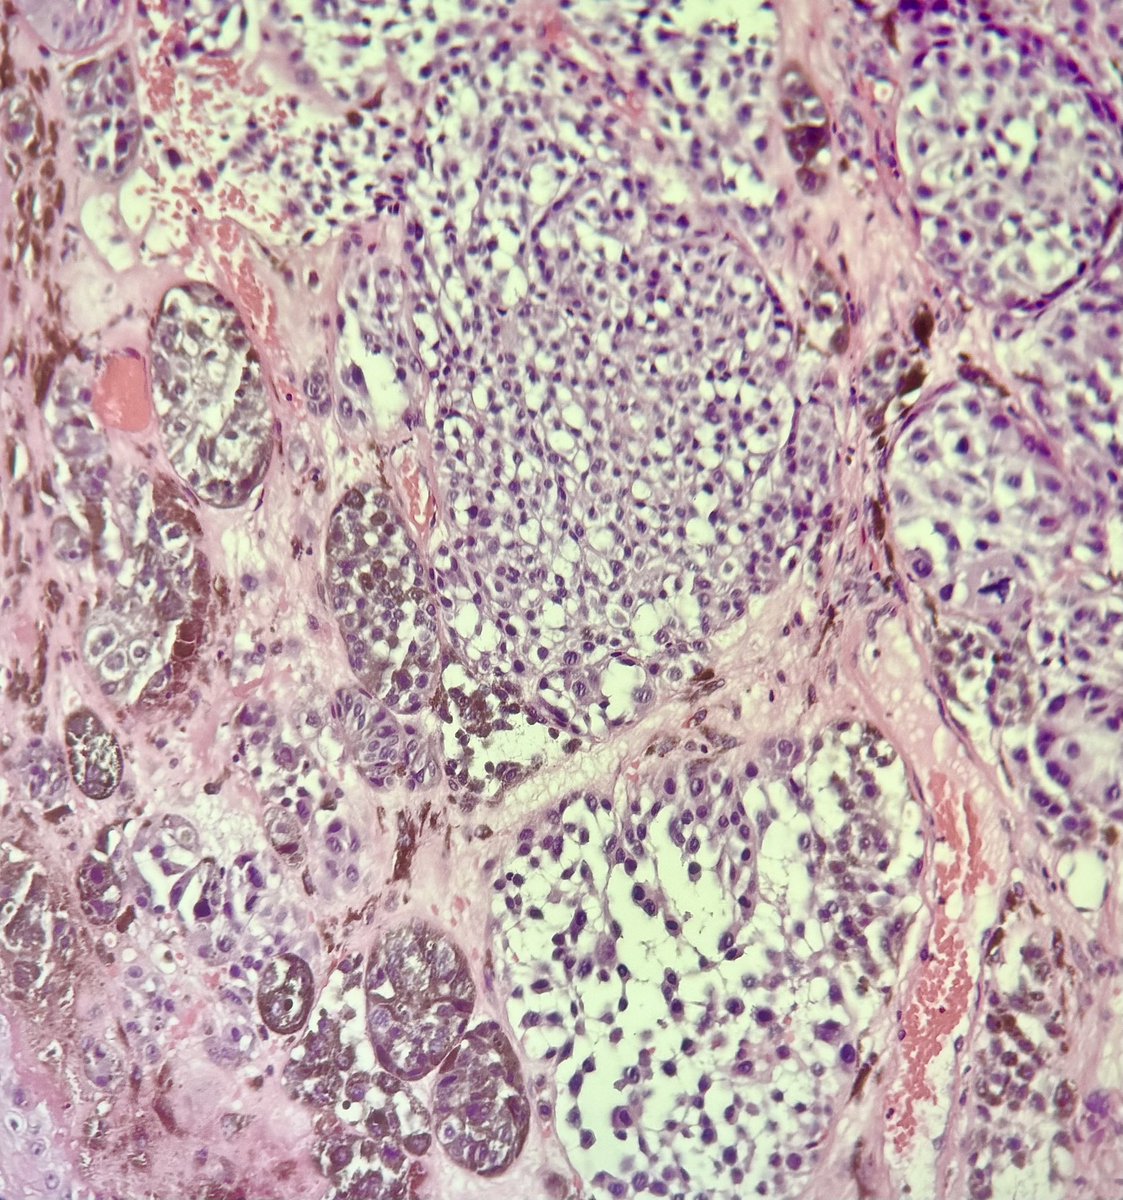

#caseoftheday Tubular adenoma (a benign adnexal tumor) that, in this case, shows tubulo-cystic, papillary, eccrine, apocrine, and hydrocystoma-like features. In more than half of cases, the BRAF p.V600E mutation can be detected #pathology #dermpath #dermatology #PathX #MedX